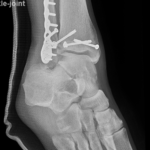

if the fracture is displaced, surgery may be needed to put the bone back into the correct position and fix the bone with Plates & screws or nails for adequate healing to occur.

- Ankle Fractures.